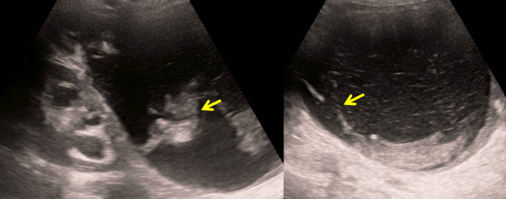

Postoperative Lymphocele in Ovarian Cancer: Radiologic Features and Diagnostic Challenges

Jabour Soukayna, Boujida Nadia, El Aitari Khadija, Omor Youssef, Latib Rachida and Amalik Sanae. 14(8): 01-04.